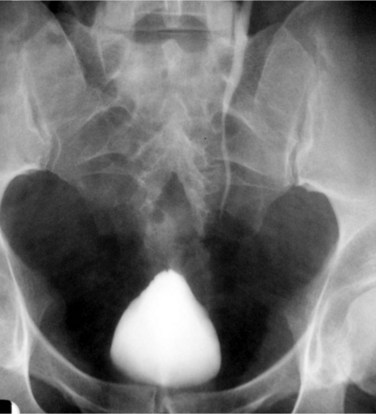

There are various radiologic signs of pelvic lipomatosis. On plain film, increased pelvic lucency may be noted (Fig. 40–13). On excretory urography, the bladder characteristically assumes a pear or gourd shape, extrinsically compressed and elongated, and the bladder base is frequently elevated (Fig. 40–14). At times, proliferation of the mature unencapsulated fat in the pelvis and retroperitoneum leads to severe bilateral hydronephrosis. In contrast to retroperitoneal fibrosis, which usually affects the proximal and midureters, pelvic lipomatosis causes significant displacement of the distal ureters medially (Lin et al, 2007). Hydroureteronephrosis may be seen (Heyns, 1991). CT is quite helpful in establishing the diagnosis, because it readily demonstrates pelvic fat (Fig. 40–15). Extrinsic compression of the rectum may also be demonstrated (Susmano and Dolin, 1979). CT may help in differentiating pelvic lipomatosis from other radiologically similar pelvic mass lesions such as lipomas, lipoplastic lymphadenopathy, and liposarcoma. Liposarcoma should be suspected if there is tissue heterogeneity, areas of positive attenuation coefficients, enhancement with contrast, and poor margination (Andac et al, 2003). MRI can also be used to make the diagnosis, because it permits characterization of fat deposits (Demas et al, 1988).

Figure 40–13 Plain radiograph of pelvis in a patient with pelvic lipomatosis. Note increased pelvic lucency.

(Courtesy of Dr. Ronald Zagoria.)

Figure 40–14 Excretory urography of a patient with pelvic lipomatosis. Note classic pear-shaped bladder with increased surrounding pelvic lucency.

Figure 40–15 Computed tomography cystogram of a patient with pelvic lipomatosis. Note narrowed bladder and increased pelvic fat in perivesical and perirectal spaces.